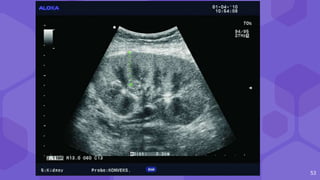

LYMPHOCELES SEROMAS

● Usg : anechoic/ hypo fluid collections

● CT round, hypoattenuating collections of clear fluid

● MRI visualizes lymphoceles, seromas and urinomas very similarly

31

Large lymphocele